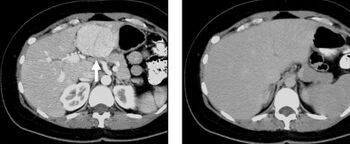

Non-contrast CT scans Figure 1a (left) and 1b (right) are of limited use for the differentiation of soft tissue structures. However, materials like blood, calcium (renal stones, vascular atherosclerosis), bone, and pulmonary parenchyma are highly visible and can usually be adequately assessed with non-contrast CT. For example, in the abdomen and pelvis, there are several indications for non-contrast imaging. These include: evaluation of renal calculi; assessment for gross intra-abdominal hemorrhage; and post-endostent volume measurements. In addition, non-contrast images are often obtained in conjunction with contrast enhanced images in evaluating potential renal transplant donors and in the evaluation of the pancreas (in combination with contrast phases). Of note, dual-energy CT and the development of virtual “non-contrast” images may ultimately obviate the combination scans. Additionally, CT angiography examinations performed for pathologies like aneurysms and dissection are frequently performed in conjunction with non-contrast imaging. The non-contrast images facilitate the differentiation of active extravasation or acute bleeding from vascular calcifications.[citation needed]

The most common technique is to perform portal venous phase imaging in the abdomen and pelvis (approximately 60–90 seconds after contrast administration, figure 2). This results in near optimal contrast opacification of the majority of the solid abdominal organs and it is used for a wide variety of indications: nonspecific abdominal pain; hernia; infection; masses (with a few exceptions such as hypervascular, renal, and some hepatic tumors); and in most follow-up examinations. As a general rule, this single phase is adequate unless there is a specific clinical indication that has been shown to benefit from other phases.[citation needed]

FIGURE 2. Contrast enhanced CT demonstrating parenchymal enhancement of the intra-abdominal organs in the portal venous phase (axial left, coronal reformat right).[citation needed]